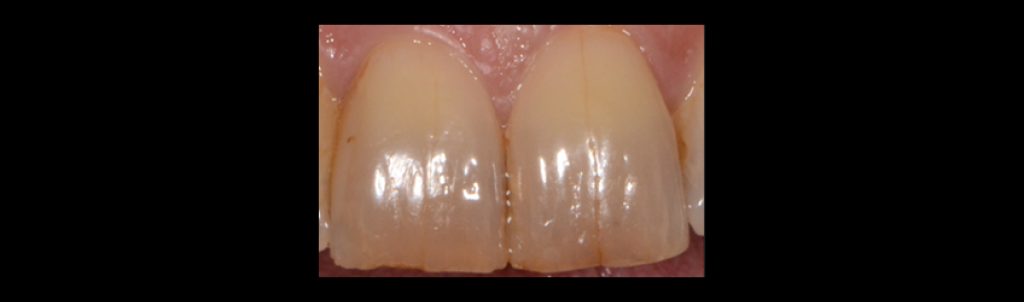

Craze lines

Craze lines are superficial enamel cracks found in both anterior and posterior teeth. They are self-limiting stress fractures in the enamel only and do not penetrate dentin. Craze lines require identification but no treatment unless staining creates an esthetic concern.